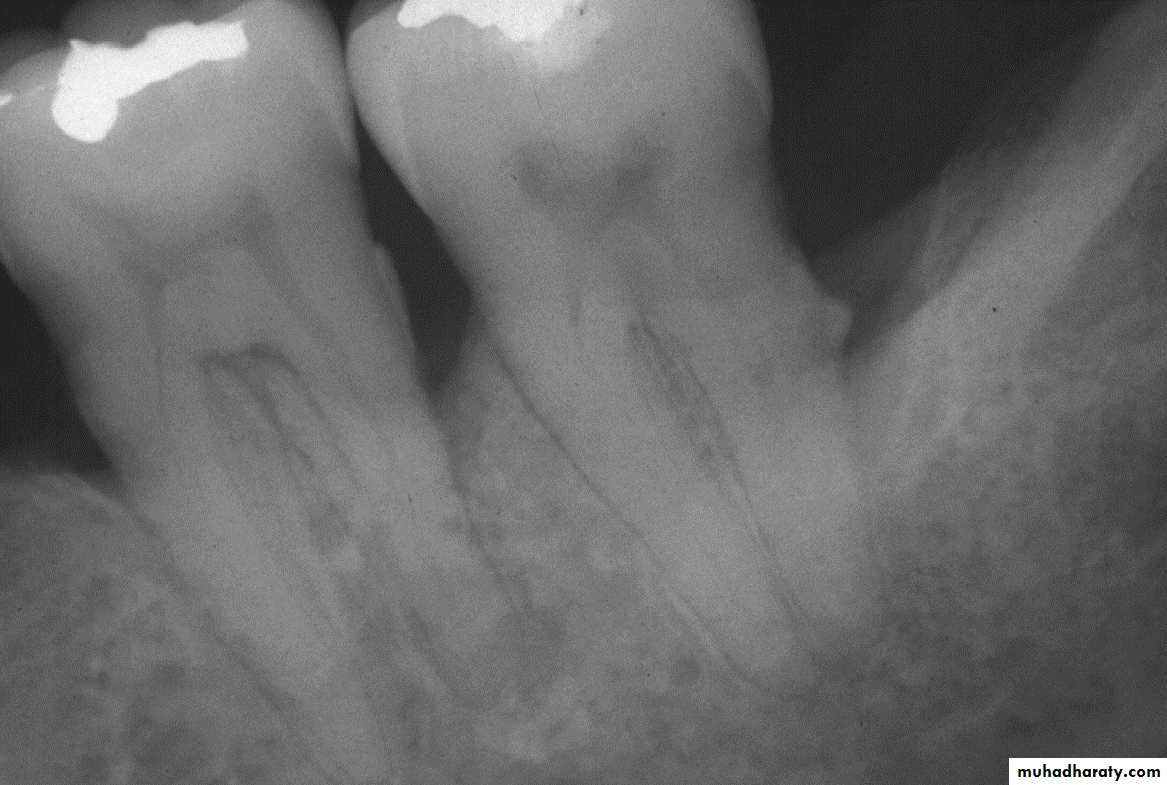

• The gingiva must be dried before accurate observations. Light reflection from moist gingiva obscures detail. In addition to visual examination and exploration with instrumentsRadiograph may sometimes reveal heavy calculus deposits interproximally and even on the facial and lingual surfaces.

• Radiographs indicate areas of bone loss where pockets may be suspected but :

• they do not show pocket presence or depth

• They show no difference before or after pocket elimination unless bone has been modified

• Guttapercha points or calibrated silver points 19 can

• be used with the radiograph to assist in determining the level of attachment of periodontal pockets

• Blunted silver points assist in locating the base of pockets